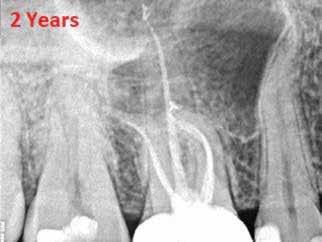

A beavatkozás során helyi érzéstelenítésben teljes vastagságú mucoperiostealis lebenyt képeztünk, és a sablon segítségével bejelöltük a preparálandó csontablak határait. Az ablak széleinek megfelelően Piezotome CUBE LED kézi-darabbal (ACTEON) a kortikális teljes vastagságában vágást ejtettünk, majd az így kapott csontlemezt (ablakot) eltávolítottuk (1. e–h. ábra), és ezt követően steril fiziológiás sóoldatba helyeztük. A rezekció elvégzését követően (1. i. ábra) a mezialis csatornákat ultrahangos eszközök segítségével (NSK) retrográd irányból preparáltuk, majd az így kialakított mélyedésbe retrográd gyökértömést készítettünk. A tömés anyagául az EndoSequence BC RRM Fast Set Putty-t (Brasseler) választottuk. A tömés elkészítését követően a csontablakot visszaillesztettük, és a stabilizálása érdekében a vágásoknak megfelelően kialakult résekbe kollagén szivacsokat (Collagen Tape, Zimmer Biomet) helyeztünk (1. j-k. ábra). A lebenyt 6/0-s Prolene varratokkal (Corpaul) rögzítettük.

A kétéves kontroll során elvégzett klinikai és radiológiai vizsgálat (CBCT-felvétel) a periapicalis elváltozások megszűnését és a corticalis csontállomány tünet- és szövődménymentes gyógyulását